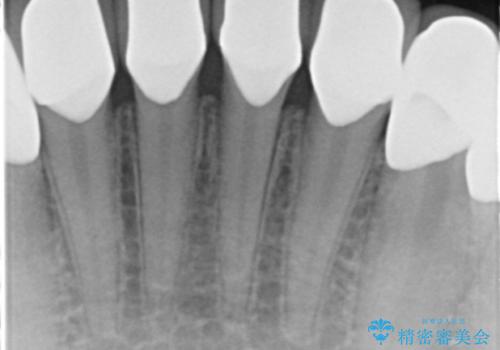

精査したところ、ほとんどの歯が保険内のレジンで充填されており、咬み合わせも悪く咬合していない歯もありました。

虫歯をしっかりと治療したのち、オールセラミッククラウンによる補綴治療を行いました。